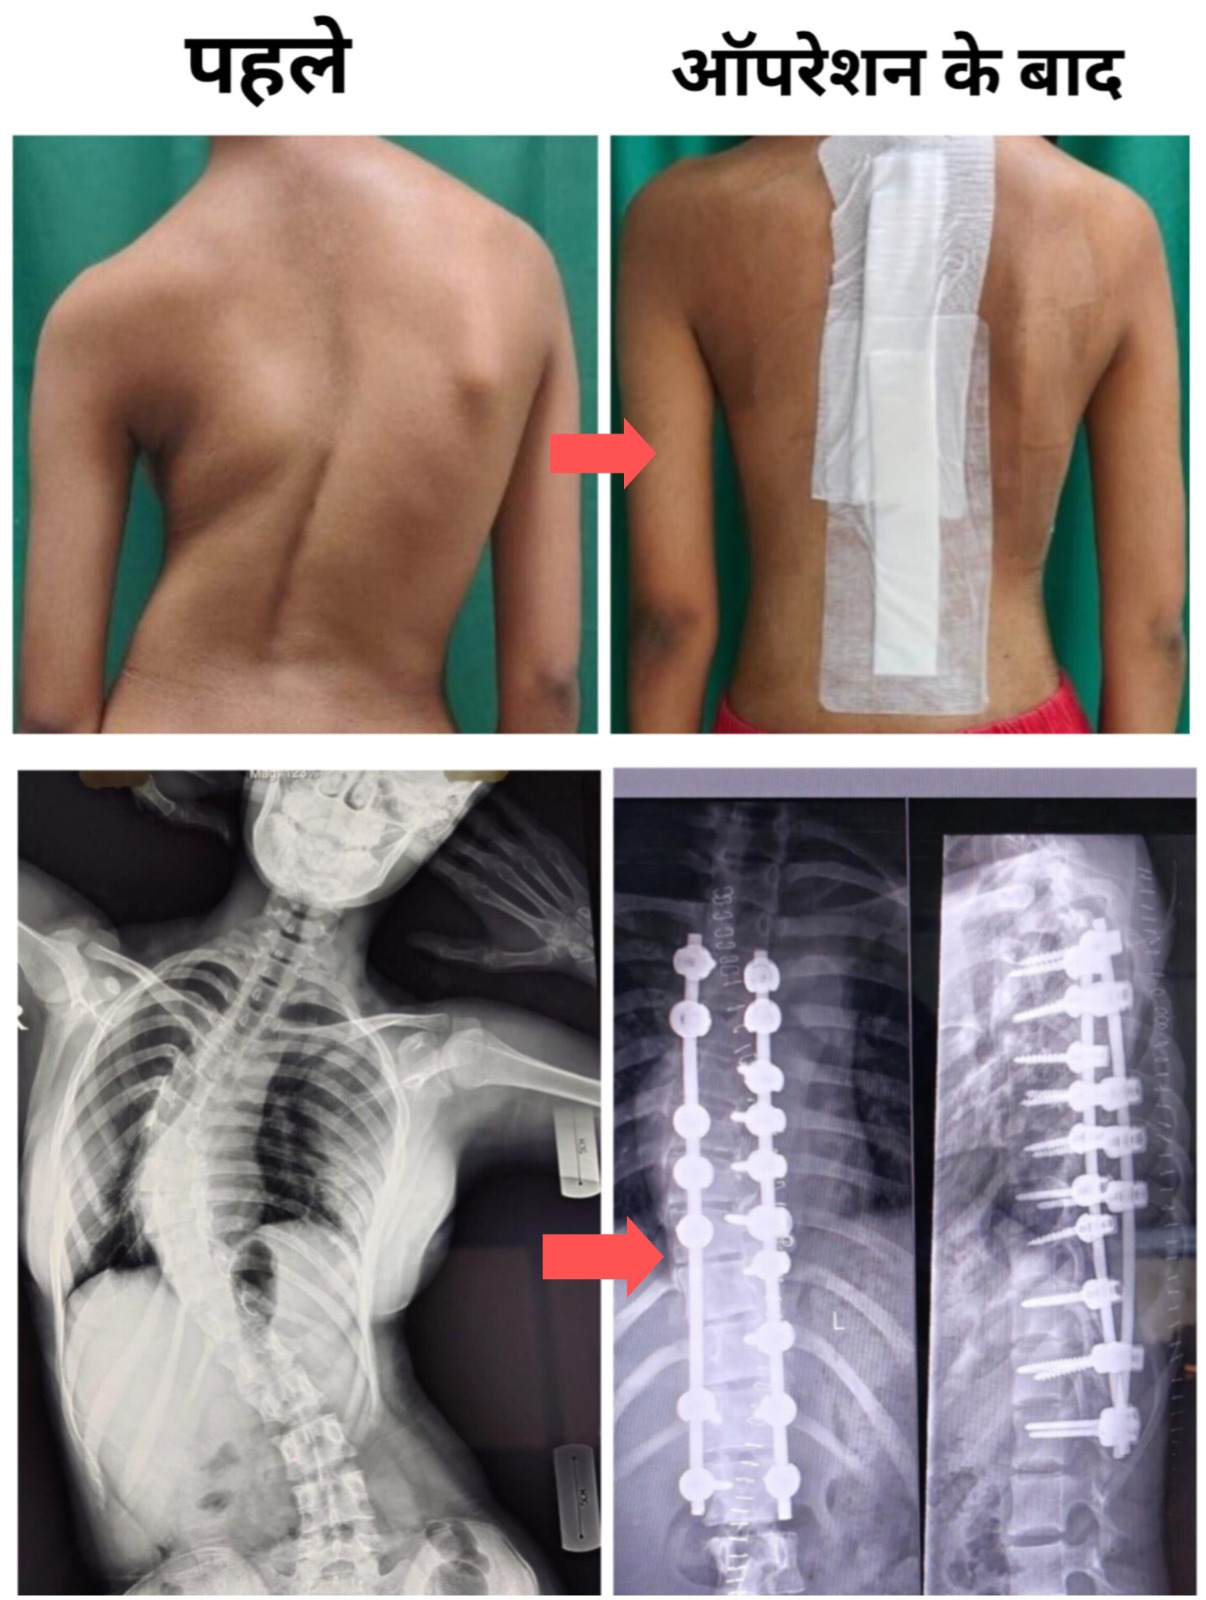

एम्स भोपाल के कार्यपालक निदेशक प्रो. (डॉ.) अजय सिंह के मार्गदर्शन में, संस्थान ने एक बार फिर चिकित्सा अनुसंधान और नवाचार के क्षेत्र में अपनी उत्कृष्टता को साबित किया है। हाल ही में, एम्स भोपाल में एक 14 वर्षीय मरीज की गंभीर स्कोलियोसिस (रीढ़ की हड्डी में अत्यधिक टेढ़ापन) की सफल सर्जरी की गई। यह जटिल ऑपरेशन एम्स भोपाल के विशेषज्ञ चिकित्सकों द्वारा अत्याधुनिक नेविगेशन तकनीक और 3डी सीटी इमेजिंग की मदद से किया गया। सर्जरी के बाद मरीज अब पूरी तरह स्वस्थ है और उसकी लम्बाई ऑपरेशन से पहले की तुलना में लगभग 2 सेंटीमीटर बढ़ गई है। यह न केवल चिकित्सकीय दृष्टि से बल्कि भावनात्मक और मानसिक रूप से भी मरीज और उसके परिवार के लिए अत्यंत सुकूनदायक उपलब्धि रही। यह सर्जरी डॉ. वी. के. वर्मा एवं उनकी टीम के द्वारा की गई और एनेस्थीसिया से डॉ. शिखा जैन शामिल थीं। इस सर्जरी की सफलता पर प्रो. सिंह ने कहा, “यह ऑपरेशन एम्स भोपाल की आधुनिक तकनीकों और हमारी टीम की विशेषज्ञता का प्रमाण है। गंभीर स्कोलियोसिस जैसी जटिल बीमारियों का इलाज अब भोपाल में ही संभव है, जिससे आम नागरिकों को देश के अन्य बड़े शहरों में जाने की आवश्यकता नहीं रह जाती। हमारा उद्देश्य है कि हम मध्य भारत के लोगों को उच्चस्तरीय चिकित्सा सेवाएं उनके अपने शहर में उपलब्ध कराएं।”